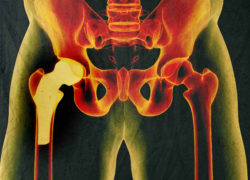

The LFIT V40 femoral head is part of a metal-on-metal hip replacement system. The femoral head fits together with the associated femoral stem through a “press fit” trunnion. This angular mismatch between the two components is supposed to obtain a reliable fixation, but Verlene claims that this connection is one of many Stryker LFIT defects.

Allegedly due to “poor design and material choices,” micro motion and fretting can reportedly occur at the connection which releases metal wear debris into the body. In extreme cases, the wear and fretting can allegedly result in the femoral head falling completely off of the femoral stem.

In less dramatic situations, the wear of fretting and release of metal debris can lead to high levels of cobalt and chromium in the blood. This metal poisoning can cause an adverse local tissue reaction, tissue and bone death, formation of fluid collections and pseudotumors, and more. These complications caused by Stryker LFIT defects can lead to the need for revision surgery.